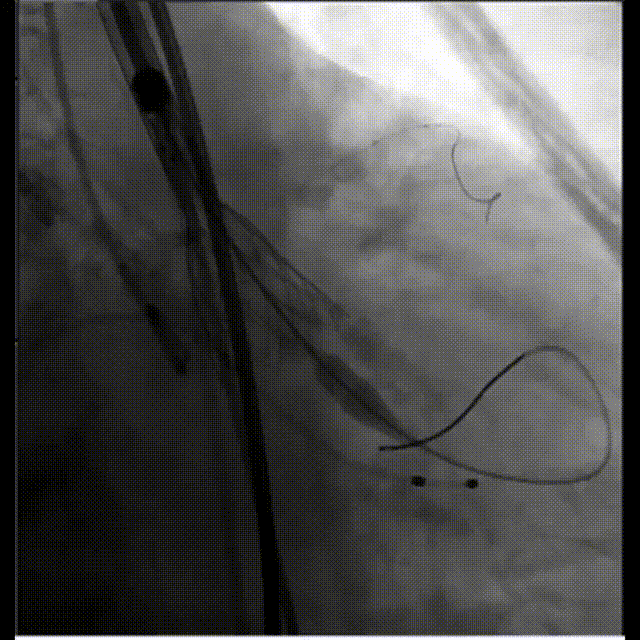

左髂动脉“翻山造影”下缓慢退鞘,造影观察无血管损伤,手术结束。

退鞘

外周血管造影